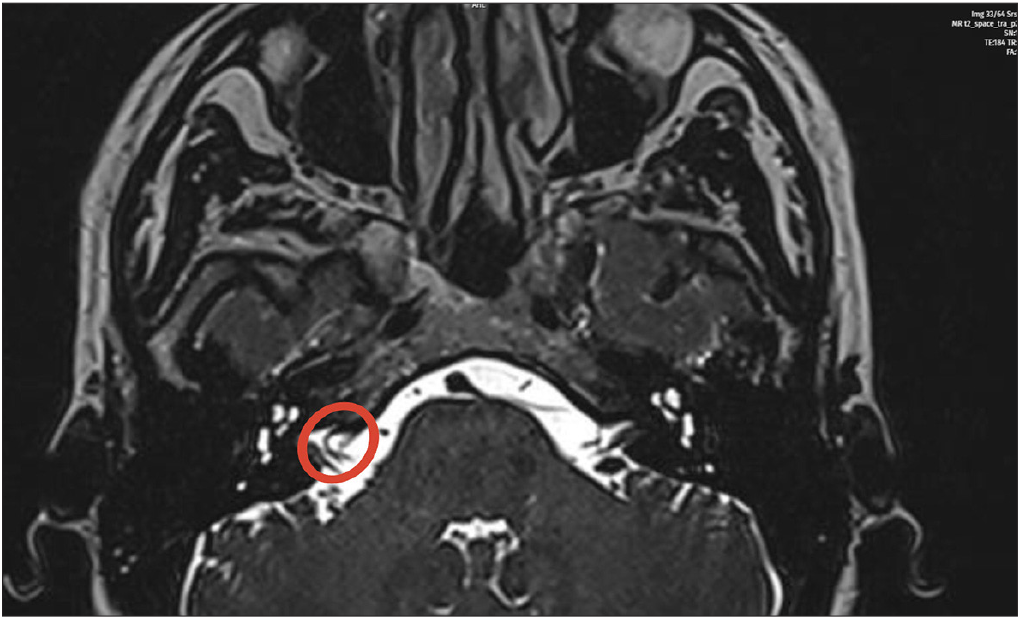

A 42-year-old female presented with acute onset of vertigo, right-sided tinnitus, and sensorineural hearing loss. Audiometric evaluation revealed a 36 dB air conduction loss and a 26 dB bone conduction loss, predominantly affecting the low frequencies [Figure 1]. MRI demonstrated that the right AICA extended into the IAC, consistent with a vascular loop [Figure 2].

- Radiological examination demonstrated that the right AICA extends into the IAC, and the findings are significant for a vascular loop (red circle). AICA: Anterior inferior cerebellar artery, IAC: Internal auditory canal.